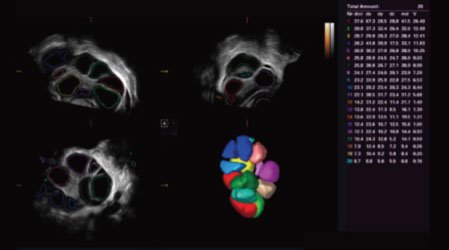

AVC Follicle

High efficiency of follicle analysis is achieved by AVC Follicle, a volume-data based automatic follicular calculation including the number and volume. Follicles are sorted by sizes in the results and rendered in different colors for better visualization.